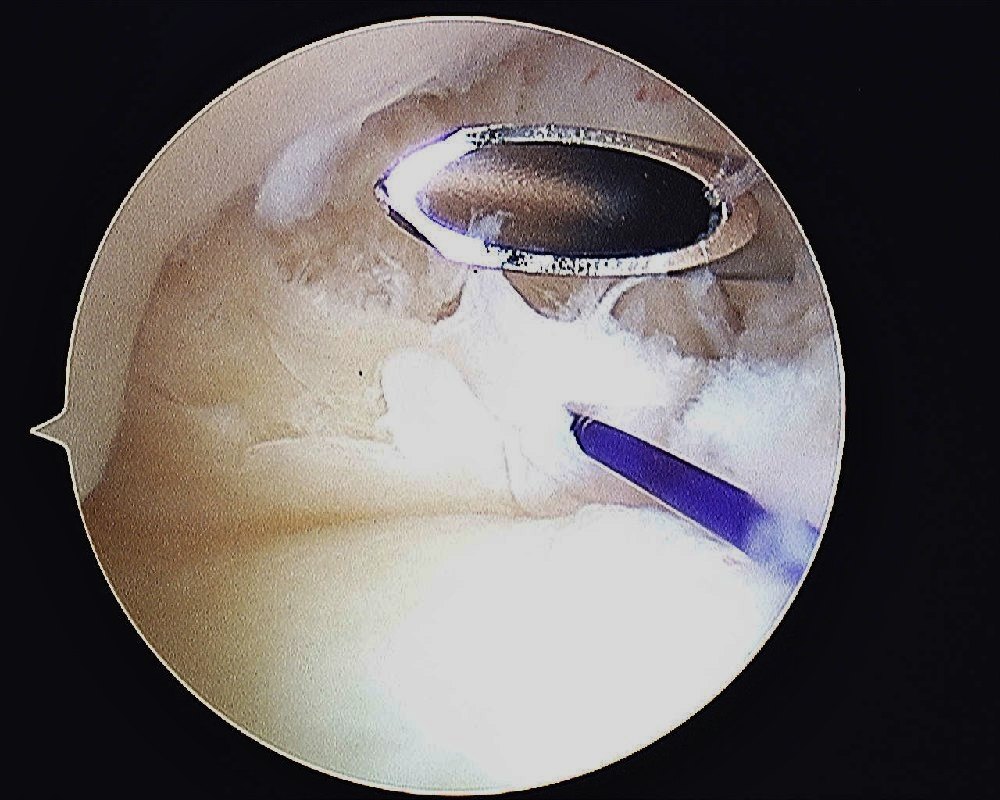

- The joint is entered using a 1.9mm arthroscope at the 3/4 portal.

- An outflow is achieved by inserting a 21G needle at the 6U.

- A working portal is created at 4/5 portal.

- The TFCC repair is done through a 6R portal which is enlarged.

- The tear is repaired with an outside in technique with PDS 3/0 suture. The Smith & Nephew’s TFCC Mender device is used to pass the sutures through the torn TFCC. The sutures are tied outside the capsule while the ECU tendon is being protected by an assistant.

- TFCC Tear – Palmer Type IB